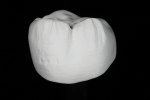

Fixed prosthetics have benefited greatly from the advancement of zirconia as a restorative material. Initially, zirconia lacked the ability to mimic natural esthetics without the additional application of labor-intensive manual techniques. This material limitation led to several techniques being developed to increase esthetics, but they required a lot of work and were not predictably replicable. Manufacturing advancements in zirconia have led to today's innovative offerings. Multilayer zirconia discs are unique in the fact that they are pre-shaded and offer a color gradient to produce lifelike esthetics (Figure 1). Manufacturers are now able to produce zirconia discs with a natural built-in transition from dentin to incisal. This natural gradient within the disc produces results similar to simple hand-built ceramic techniques. With multilayer zirconia as the restorative material, laboratories are able to utilize CAD/CAM technology to its fullest ability (Figure 2).

Post-process finishing has now become very predictable and replicable when implemented correctly in the modern laboratory. The restoration is designed in full contour, then milled, and green stage finished by applying surface texture and characterization (Figure 3 and Figure 4). While not required under most manufacturer recommendations, this is truly where the technician's artistry helps bring the true potential of the material to life.

The global acceptance of zirconia in dentistry has been a revolution. This is partly due to limited tooth preparation requirements, allowing dentists to utilize preparation techniques they have become accustomed to over many years (Figure 5). After sintering, the restoration is final adjusted and checked for accuracy on the die. Once the restoration is verified as accurate, a simple stain-and-glaze technique easily achieves individual characterization of the final restoration (Figure 6). The implementation of multilayer zirconia allows for a predictable digital workflow from diagnostic wax-up to final restoration. These esthetic results were previously only possible with labor-intensive layering techniques (Figure 7 and Figure 8) but are now achievable in single-unit cases to full-mouth rehabilitations without the need for ceramic application (Figure 9).